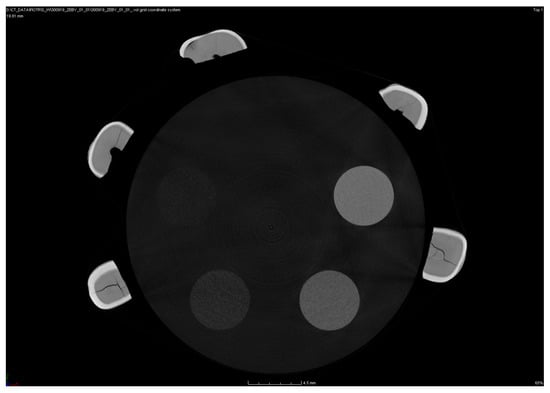

The v|tome|x microtomography system (General Electric, Cincinnati, OH, USA) was used in this study. Each tooth was placed on a polymer base and scanned simultaneously, with the density pattern at 130 kV. After passing through the sample, the X-radiation was converted to visible radiation using the Yttrium Aluminum Garnet (YAG): Ce scintillator, allowing the image to be recorded with a resolution of 2024 × 2024 pixels. For each tooth, 1450 scans were recorded at a total scan time of 64 min/tooth and a current of 165 μA. The distance of the sample from the matrix was set in such a way so as to obtain the maximum image resolution, i.e., the smallest possible voxel. Projections were acquired every 0.4° with a total rotation of 180°. To improve the signal-to-noise ratio, the measurements from every three acquisitions were averaged at every step of the tooth’s rotation. Thus, the determined parameters allowed us to obtain microtomograms with optimal contrast and a resolution of 20 μm. The acquisition of microtomographic scans of teeth was carried out in 8-bit grey scale in order to identify changes in the density of the analyzed objects as accurately as possible. Due to the small size of the teeth, the acquisition of microtomographic scans was carried out simultaneously for five teeth and density patterns.

In order to determine the density of individual tooth elements, their microtomographic scans were analyzed. An example of a microtomographic scan is shown in Figure 3, which shows five premolars and a density template.

Figure 3. An example of a microtomographic scan containing five premolars with a density template.